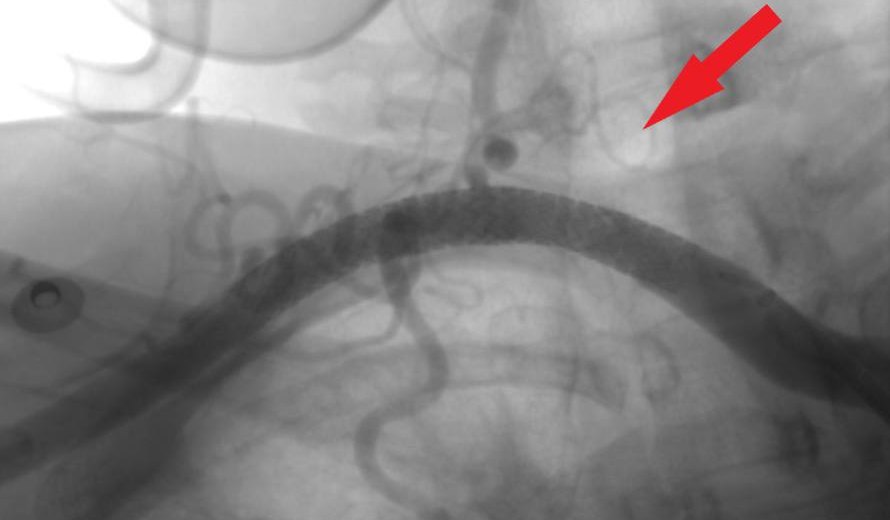

Дообследование пациентки показало серьезное поражение сразу нескольких сегментов артерий руки. Был выявлен тромбоз плечевой артерии (также артерий предплечья и артерий кисти) в сочетании со стенозом подключичной артерии.

Далее женщину перевезли в операционную рентгенэндоваскулярной хирургии, где уже с помощью раздувания небольшим баллонным катетером (2 мм) выполнено восстановление кровотока в артериях предплечья и кисти, после этого на подключичной артерии пораженной конечности была выполнена баллонная ангиопластика со стентированием (расширение сузившейся артерии с помощью специального стента).